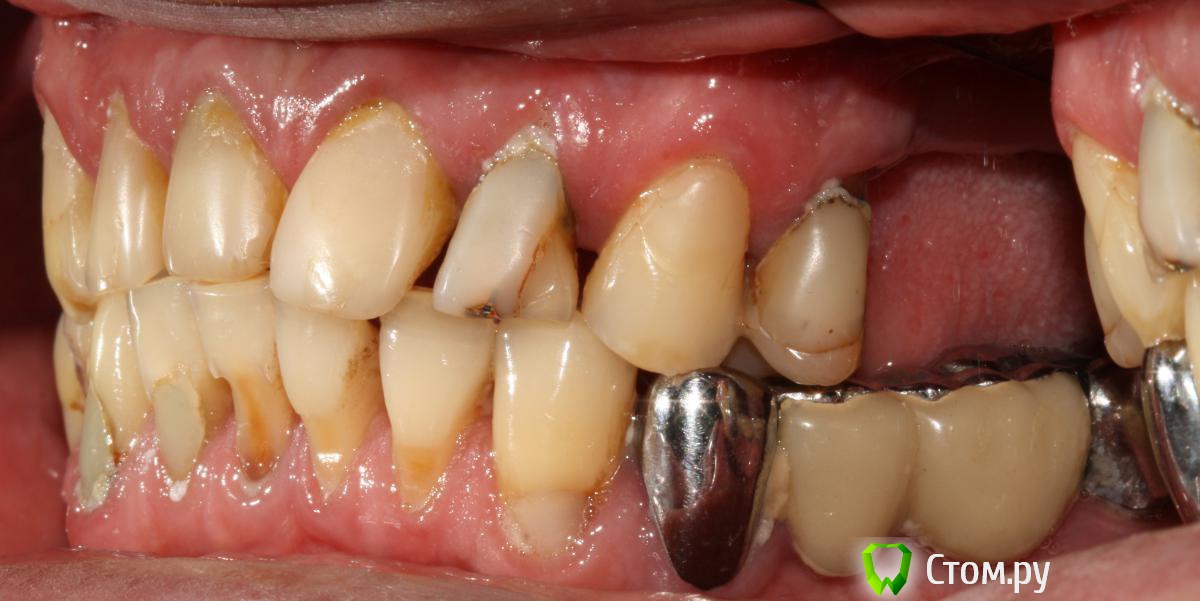

Привет всем! уважаемые Гуру помогите с планированием реабилитации данного пациента. Основная жалоба, не хочет носить съемный протез (пришел из другой клиники, где рекомендовали только съемное протезирование).

Провели обследование. Ортопед планирует оставить вверху 6 фронтальных зубов (возможно резцы пойдут на удаление), внизу только клыки. Далее последует удаление несостоятельных зубов + иммедиат протезы, продолжение реабилитации.

п.с. ДА, С ГИГИЕНОЙ ПОКА ЗАСАДА!!!)